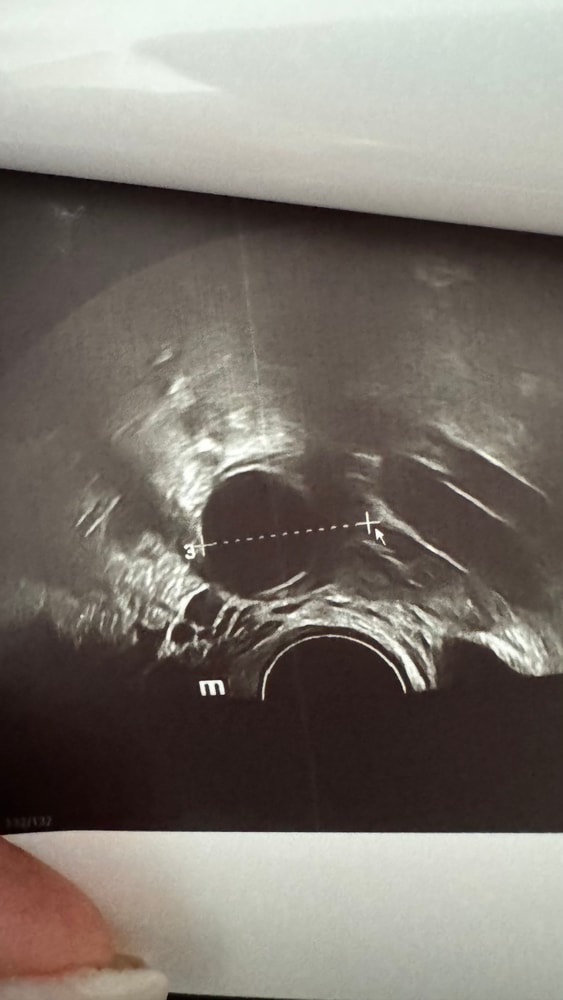

ДФ 24 мм, на 17 дц

узи :дф 24 мм, эндометрий 13мм однородный.

Таня, блин, сложно конечно, может я ошибаюсь, но на фото 👆с линейкой и цифрой 3 это же размер яичника. ДФ черным, и линейка явно не его мерит. Нет? Не понимаю.